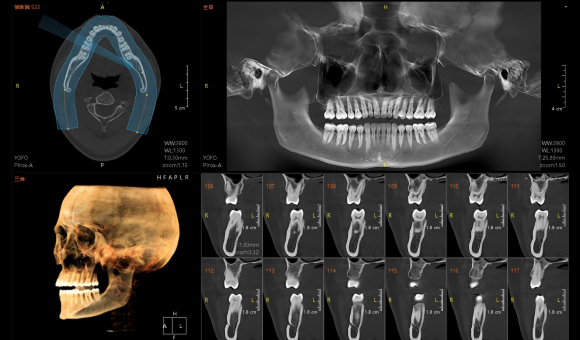

只需一次单圈扫描即可获得CT、3D全景和3D正/侧位影像,并能同时生成3D TMJ视图

提高诊疗效率,避免过度检查,减少患者所受的辐射

• CT

CT

• 3D全景

3D全景

• 3D 正侧位

3D 正侧位

• 3D TMJ视图

3D TMJ视图